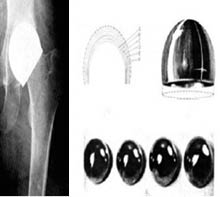

En 1923 aparece el primer antecedente de una prótesis en copa llamada "artroplastia de molde" de N. Smith-Petersen (Figura 3), el concepto de esta intervención sólo se concentraba en la cabeza femoral, exponiendo el hueso esponjoso y colocando una copa sobre ella. Los primeros implantes fueron de cristal, los cuales en pocos meses se rompían, posteriormente utilizó la celulosa, sin embargo, dio reacciones de cuerpo extraño, le siguieron el uso de pirex y baquelita. Al llegar 1938, se describe el primer material metálico biocompatible: vitalium, el cual se compone de una aleación cromo-cobalto-molibdeno.1,6 En el año 1939 Smith-Petersen presenta su técnica,8 en 1947 presenta la evolución de esa cirugía,9 y posteriormente presentaría mayor cantidad de resultados10 e incluso presentaría la mencionada técnica como alternativa para fracturas,11 pero el tiempo pasaría, hasta 1957 cuando Aufranc publicaría un artículo con 1,000 casos de caderas operadas con buenas consecuencias, con la técnica previamente mencionada.12

Las prótesis articulares han revolucionado la ortopedia conocida desde su creación, modificando la historia y dando una resolución a patologías que antes no tenían un gran pronóstico, a pesar de iniciar como tratamiento de otras enfermedades infecciosas, pasar por un proceso de ser la alternativa de fracturas y llegar hasta la actualidad donde son la principal alternativa de tratamiento para enfermedades crónico-degenerativas articulares (Figuras 10 y 11).